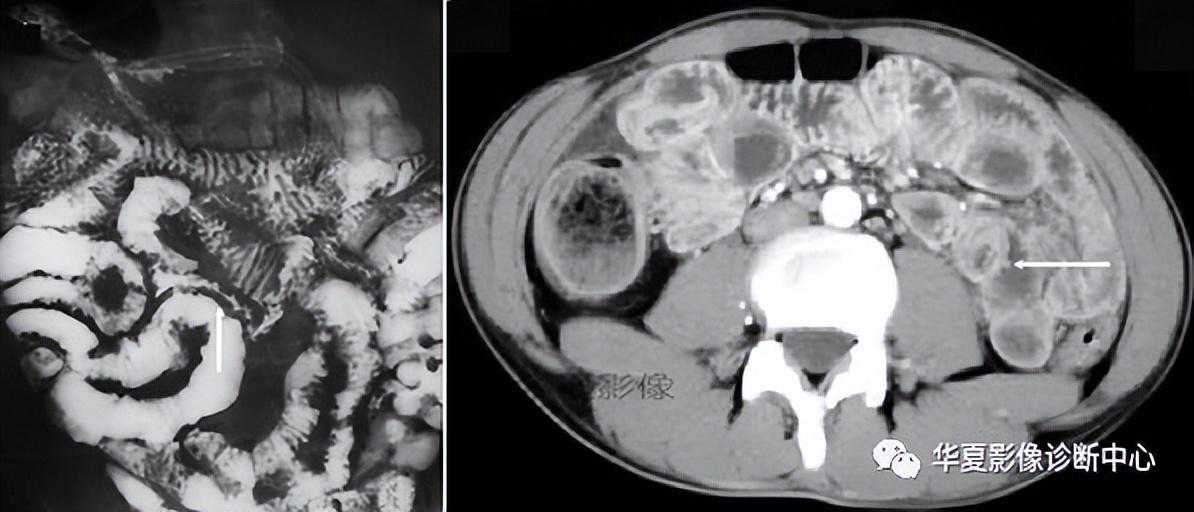

001:胃肠细绳征胃肠细绳征又名胃肠线征、绳征、绞索现象等。【影像表现】在小肠钡剂检查中,小肠形成类...